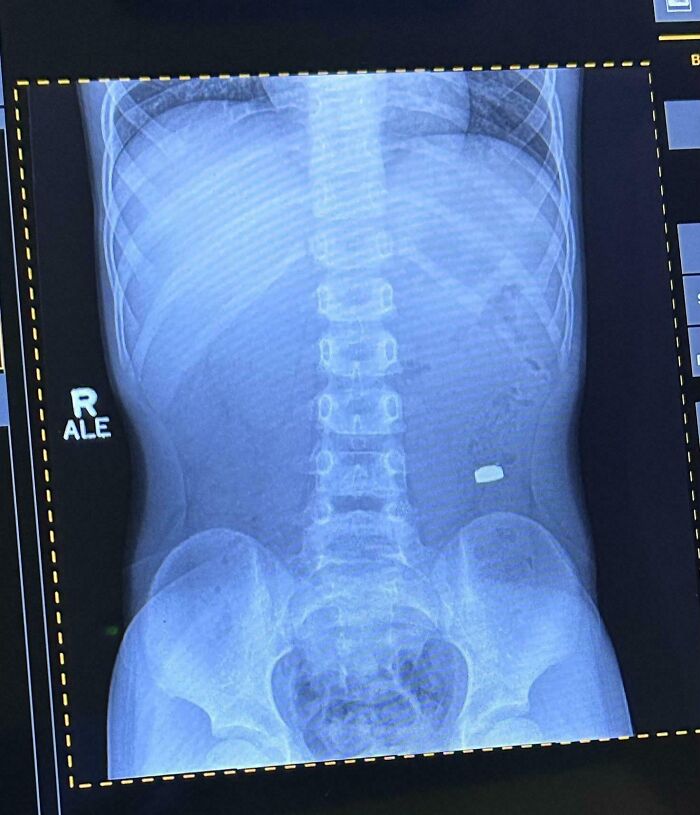

Môj syn zjedol batériu